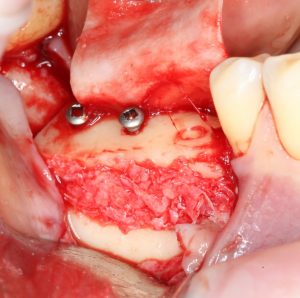

Сделать это не просто, а очень просто: мы просто обрабатываем принимающее ложе, снижая толщину компактной пластинки (вплоть до полного её удаления) и одновременно увеличивая площадь контакта с графтом:

Причём, целесообразно проводить такую манипуляцию даже в случаях, когда мы используем НКР-методы, а не только при аутотрансплантации блоков:

Обработка принимающего ложа или, если хотите, «декортикация» или «декомпактизация», преследует еще один важный момент. При разрущении кости, даже в очень небольших объемах, образуются факторы роста костной ткани, инициирующие остеогенез. А этого мы с вами, в общем-то, и добиваемся.